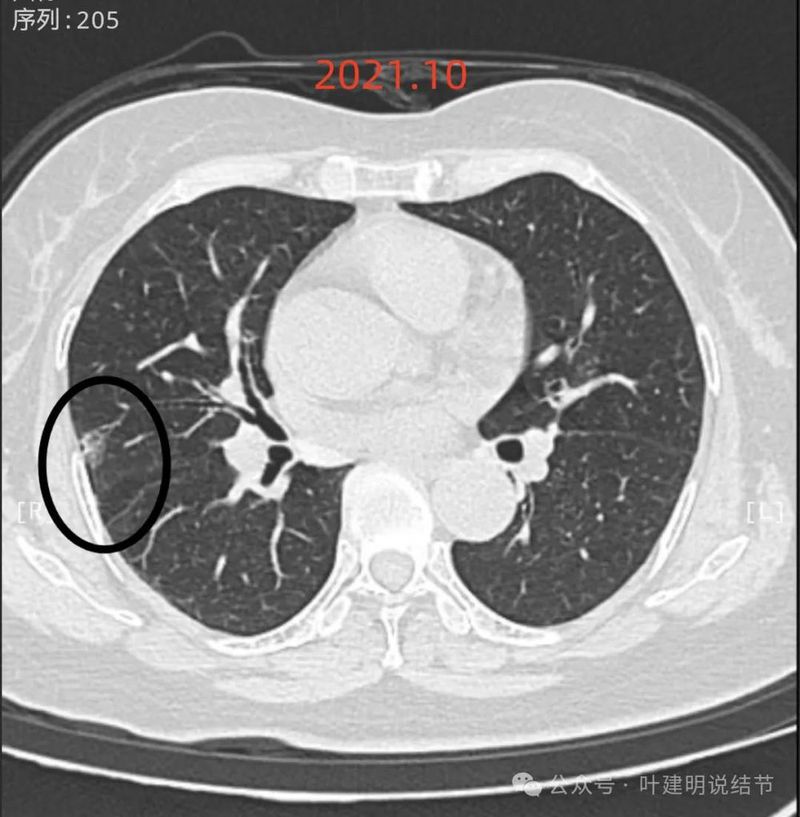

先看2021年10月时的影像:

右中叶胸膜下磨玻璃影,有血管进入,贴着胸膜,密度不纯,但收缩力不显著,灶内有小空泡征。肿瘤范畴的可能性大些,微浸润性腺癌或浸润性腺癌贴壁为主型。